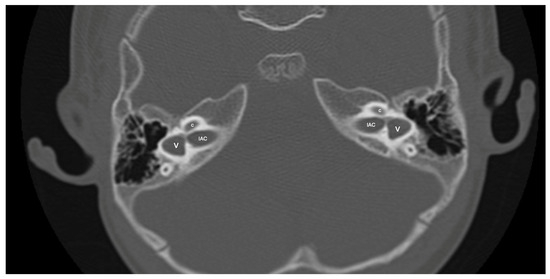

Figure 3.

Patient with right-sided IP-1 (incomplete partition type-1) and left-sided LA (labyrinthine aplasia). On the right side, the cochlea (c) and the vestibule (v) are clearly differentiated. The cochlea has a near-normal size but lacks the entire modiolus and interscalar septa. None of the labyrinthine structures except the dense otic bone (*) can be seen on the left side.